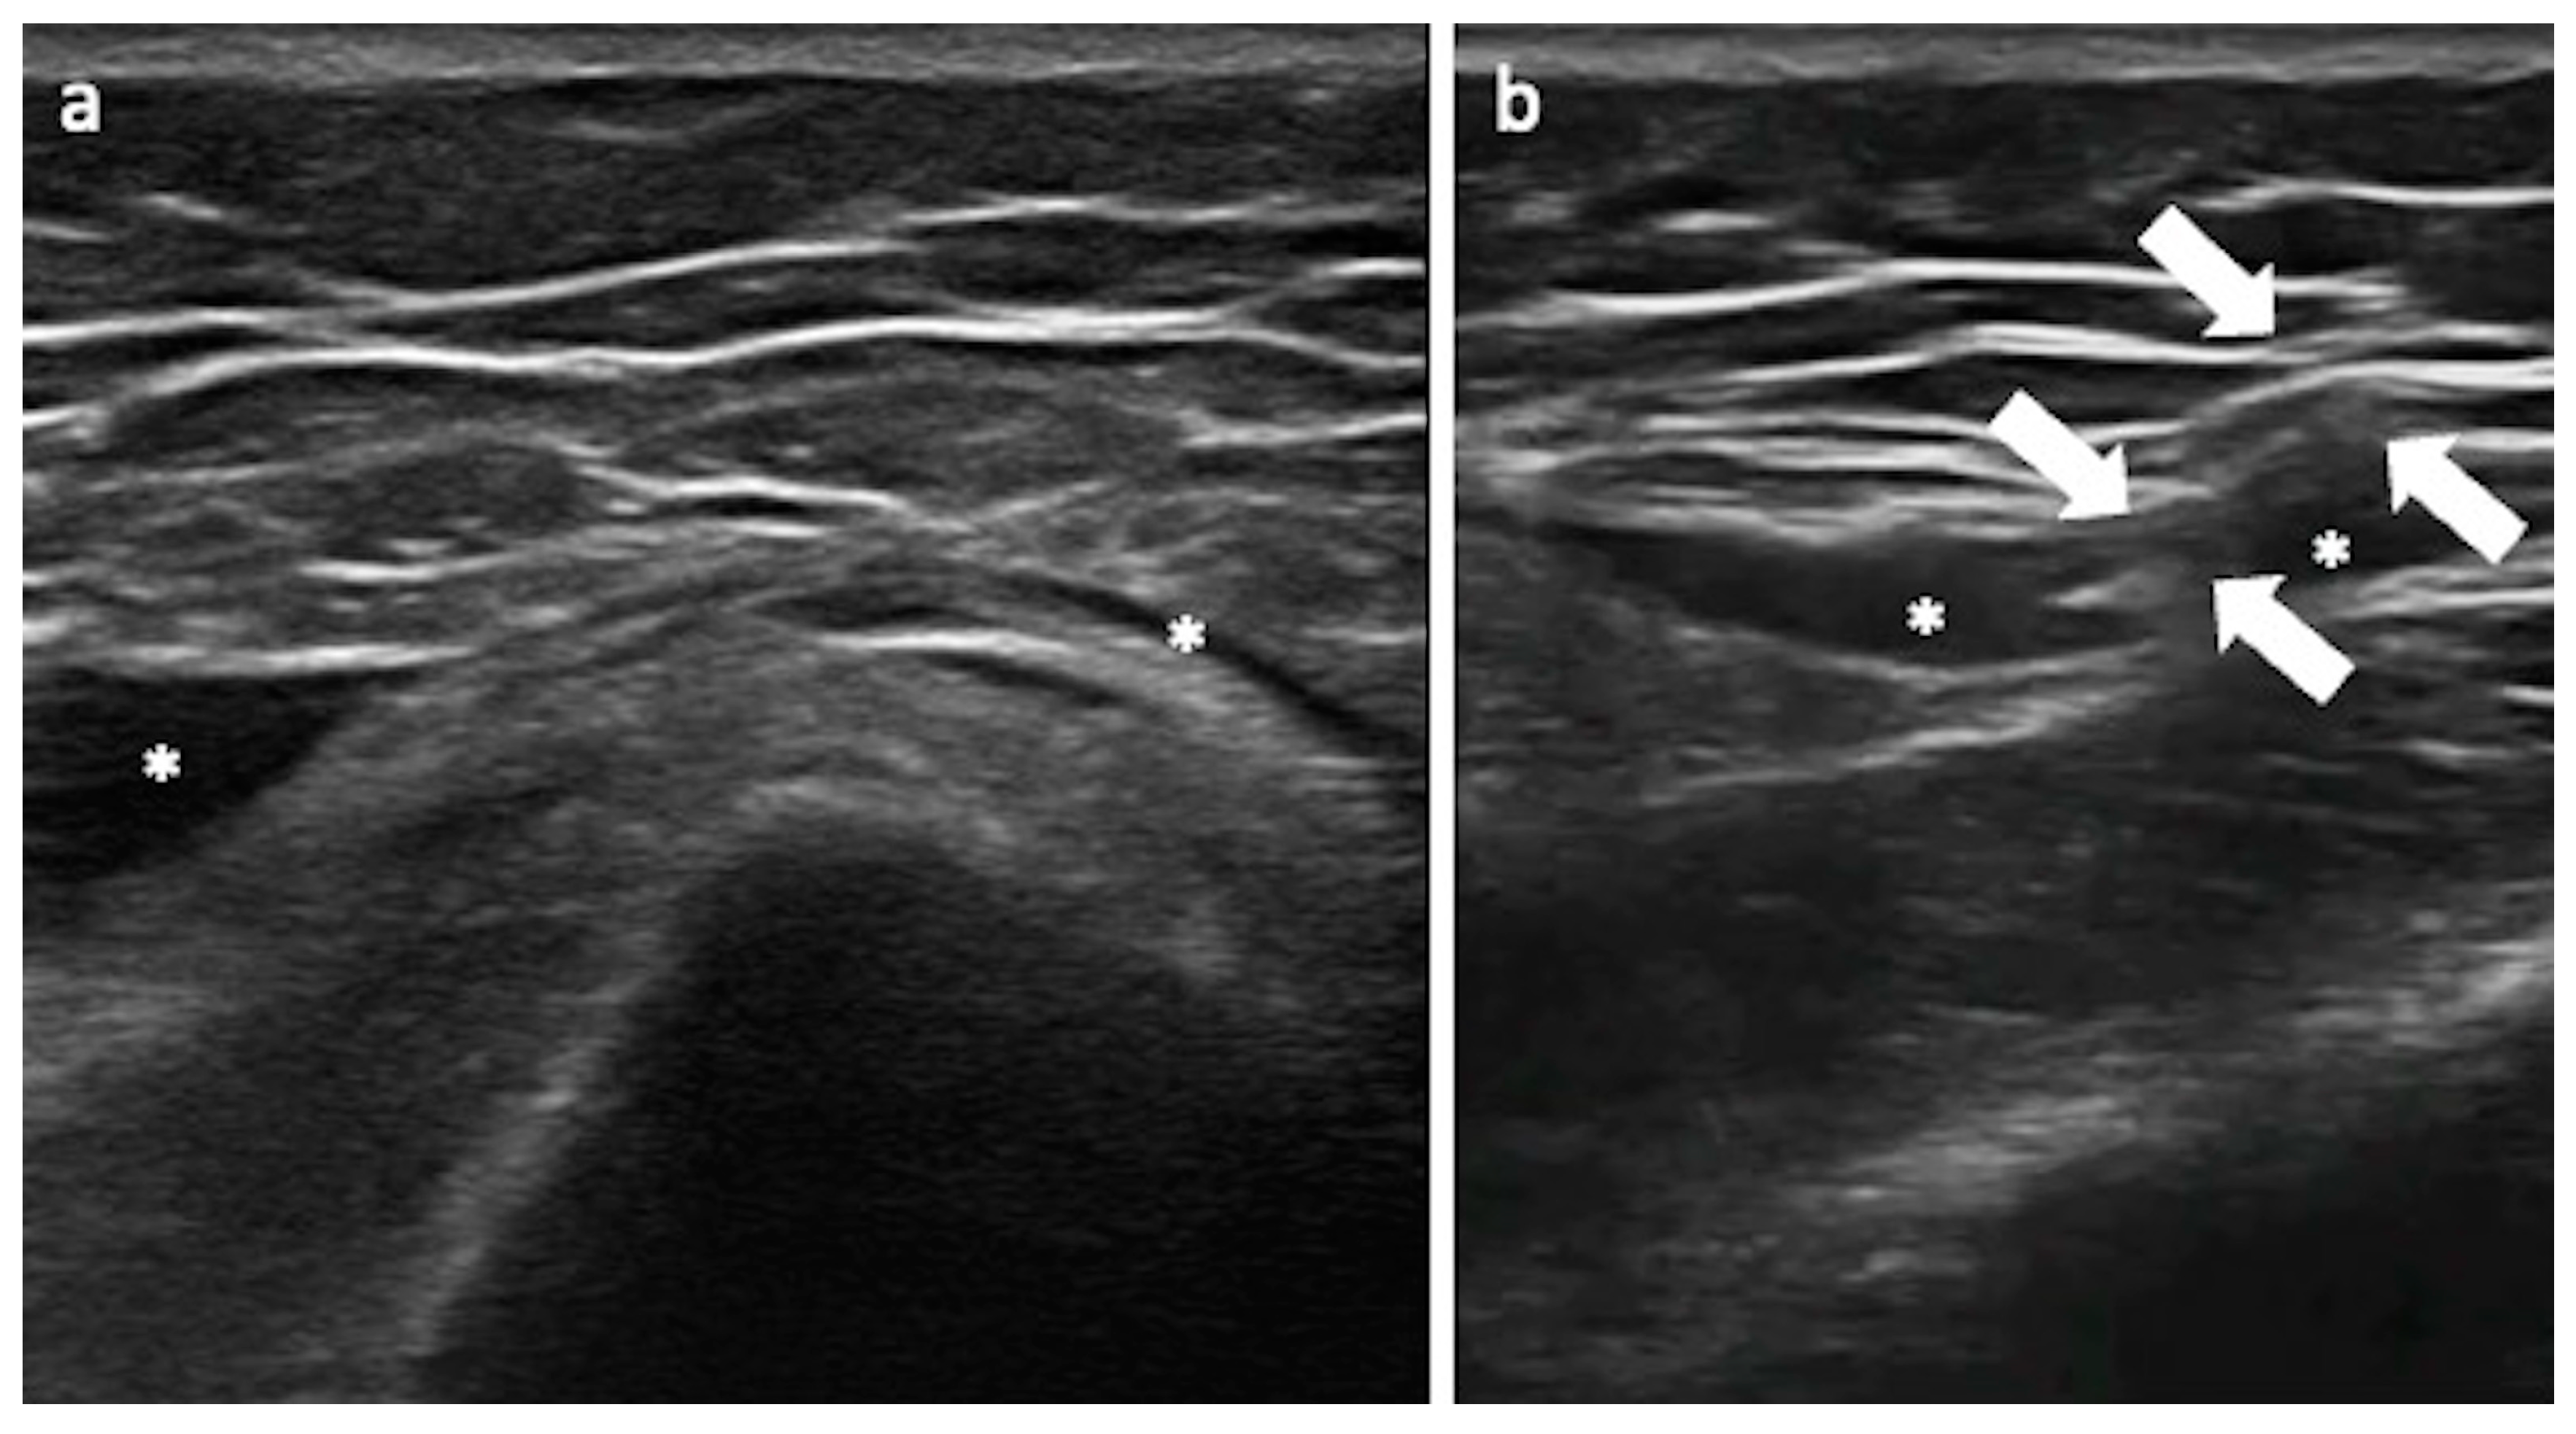

3.3. Greater Trochanteric Pain Syndrome

Technical Considerations